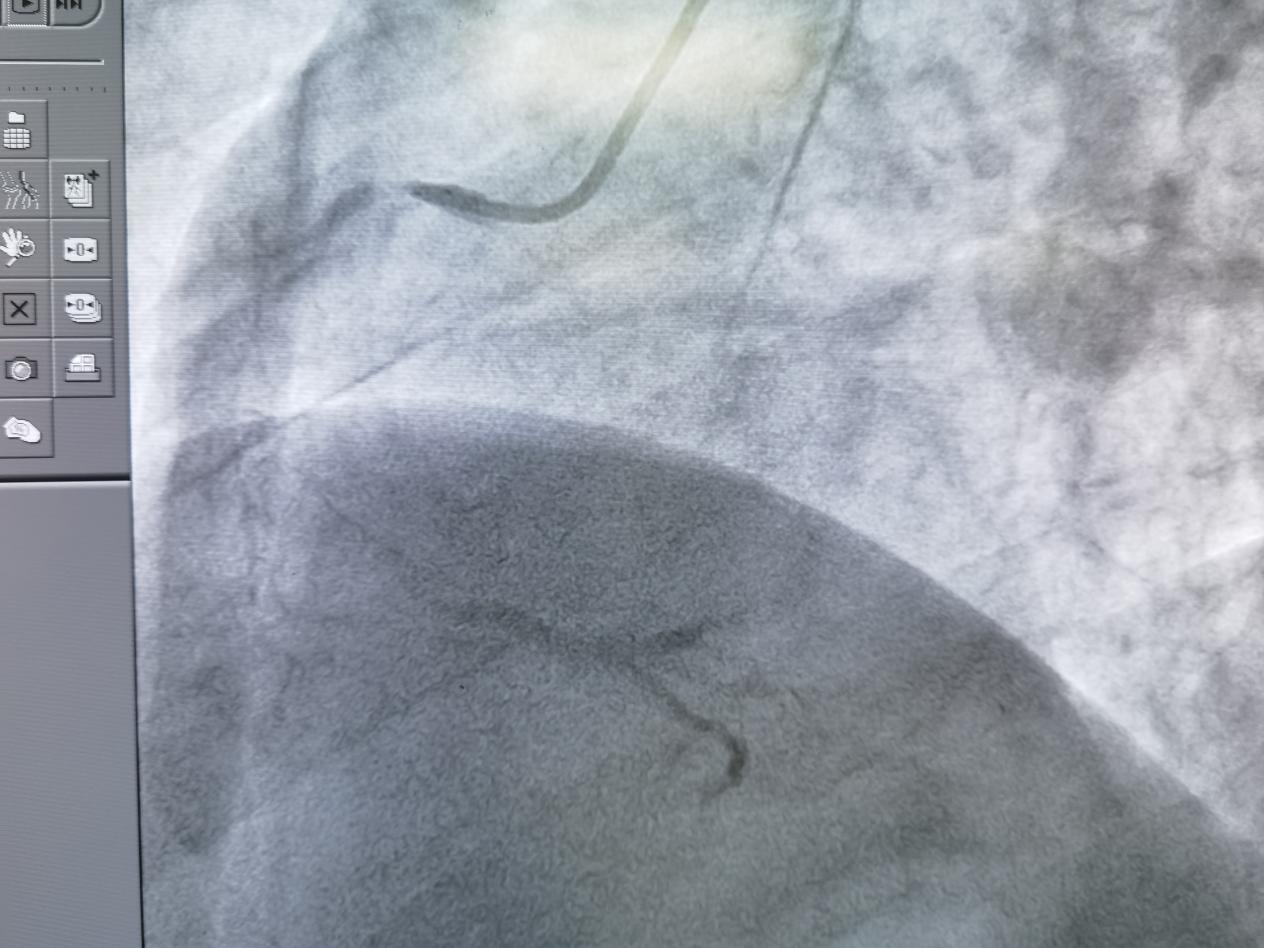

成功开通血管

手术中